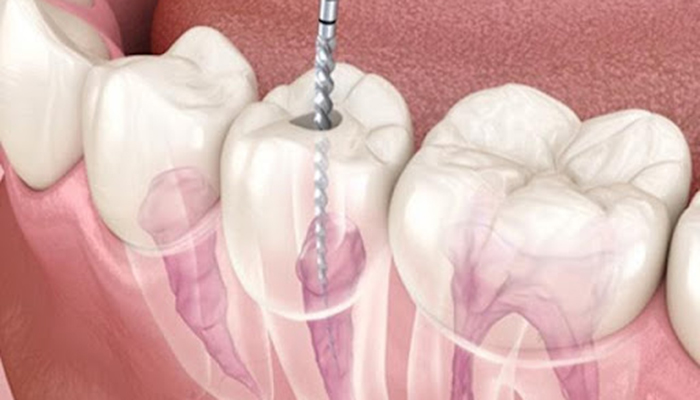

根管治療の具体的な治療内容

歯の根っこ(神経)の中から痛みや腫れの原因である「感染した汚染物」を、取り除く治療です。

針のような道具を使って、感染した汚染物をとりのぞいていきます。

汚れを取り除いた箇所をキレイに清掃・消毒して、お薬で埋めるまでが根管治療です。

ニッケルチタンファイル

歯の神経の治療の際に、根の曲がりが強すぎると従来のステンレスの器具では根の先までのアクセスするために、歯の上部をより多く削らなければなりませんでした。

ニッケルチタンファイルを使用すると、根っこの形態が従来に比べてそのまま維持された状態で根の先にアクセスできるようになりました。

再治療の時など、根っこの形態が保存されているか否かで成功率に差が出てきます。

当院ではCTで根の状態を評価し必要に応じてニッケルチタンファイルを使用します。